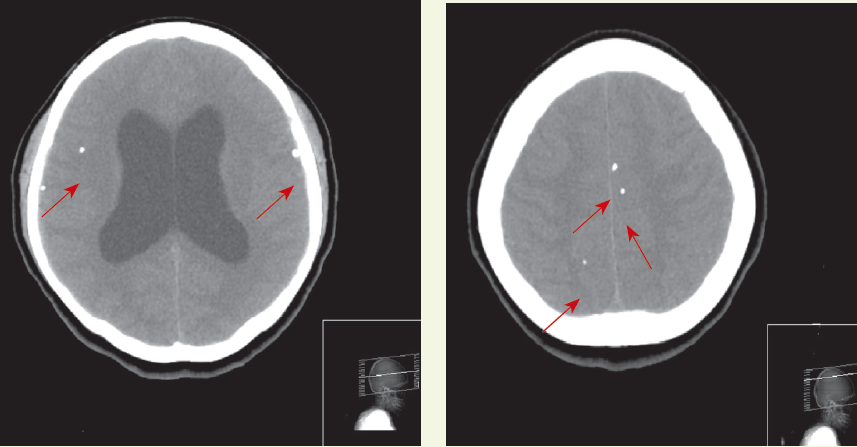

Outcome of the case. The patient in this case had already received a diagnosis of metastatic adenocarcinoma that was clearly progressive. An MRI scan of the brain revealed multiple meningeal metastases (Figure). No further investigations of his numb chin syndrome were undertaken. It was believed that the meningeal metastases were the cause of his symptoms, and he started whole brain radiation after completing the local radiation to his epidural metastasis. He may have had a mandibular metastasis, but obtaining this information would not have affected his already poor prognosis. He was referred to hospice care. ■